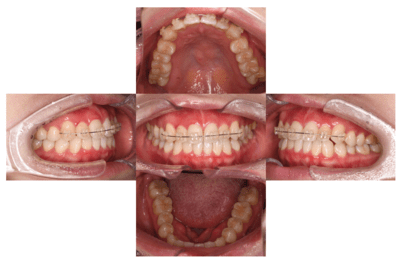

症例⑥

前歯の歯並びがきになる

| 年齢 | 20代女性 |

|---|---|

| 主訴 | 前歯の歯並びがきになる |

| 治療内容 | プチ矯正(上顎のみ) |

| 治療期間 | 2ヶ月 |

| 費用 | 165,000円(税込) (2022年2月現在) |

| リスク・副作用 | プチ矯正は全ての方に適応になるわけではありません。矯正中は器具が唇に接触するため口内炎ができやすくなります。歯が動かないなどで期間が長くなることもあります。 スペースをつくるために歯を削ることがあります。 |

| 治療方針 | 以前マウスピース矯正をしていたが、後戻りで前歯がやや前方にでてきてしまっています。 上顎下顎ともにあともどりがあり、歯と歯の間に若干スペースができている。 患者の希望が上顎だけだったので、下顎はそのままで、上顎のみ矯正をすることとした。 矯正は基本的にはスペースを作るため歯を削ることが多いが、今回のケースではスペースを閉じるだけなので、歯を削らずに行う計画を立てた。 |

ブラケット・ワイヤー装着

まずはブラケットを装着。審美的になるべく阻害がないように、透明なブラケットを使用した。

2週間後

ワイヤーはまだたわみがあるが正中はやや閉鎖してきた。

更に2週間後

正中はほぼ閉じた。ワイヤーのたわみも無くなってきた。

もうすこし左上2が頬側に出てほしい。

完成。

保定もかねてワイヤー(1622SS)変更。

1ヶ月後

ブラケット除去。

同時に予定していた保定装置のマウスピース用の印象をおこなった。

正中離開、左上2の位置、被蓋関係、全ての改善をすることができた。しかもたったの2ヶ月!

翌日、ハードタイプ1ミリのマウスピースを保定装置として使用させるために作成しお渡した。

ビフォーアフター写真

治療前

治療後